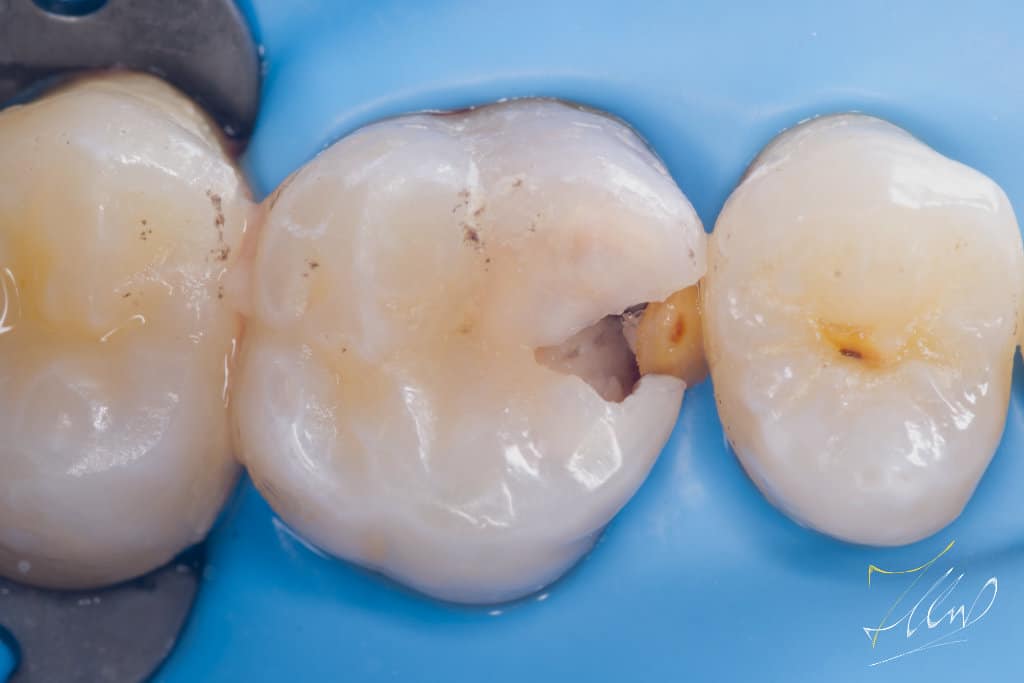

Upon initial examination, the patient reported experiencing temporary cold sensitivity and food stagnation in a specific area. The clinical diagnosis indicated that the tooth was vital, based on the Electric Pulp Test (EPT), the tooth is regarded vital, with initial response at level 36, followed by relief after 15 seconds.

When caries are removed and the pulp is exposed, it can weaken the enamel. In such cases, it is advisable to create a silicone index after covering the exposed pulp with mineral trioxide aggregate (MTA). This should be followed by a precise cavity design and the removal of unsupported buccal cusp .